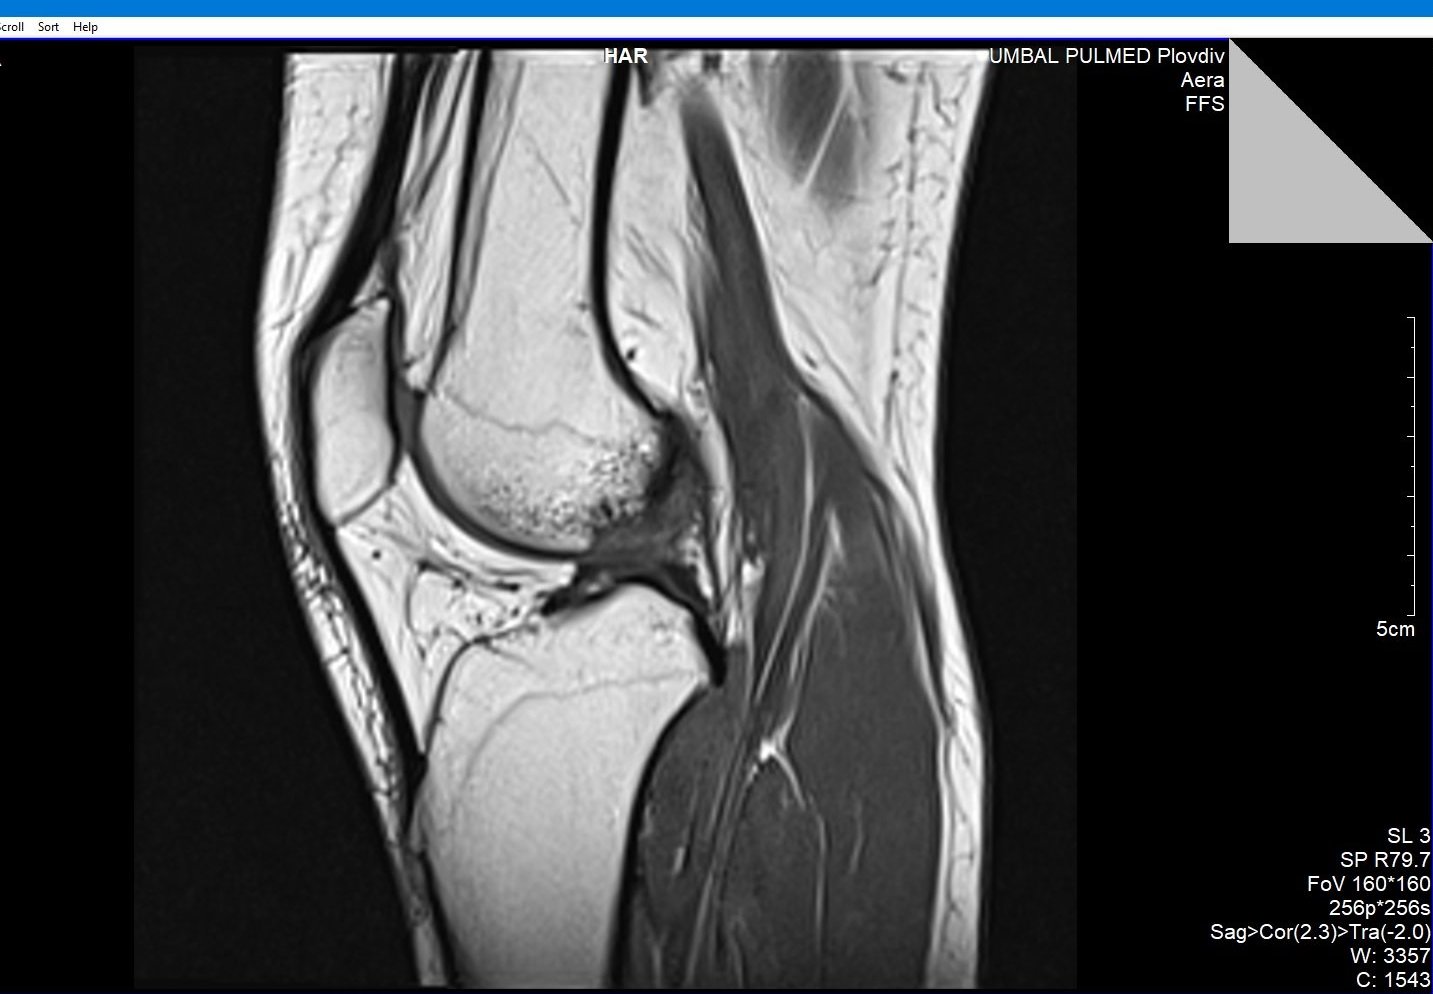

Здравейте, тъй като незнам как да ви кача целия диск Ви качвам малко снимки

Здравейте, благодаря за ЯМР-а.

Подборът на срезове/снимки не е най- добрият. Моля да изпратите диска на имейл: infо@beta-clinic.com или чрез спедитор на адреса на Бета клиник.